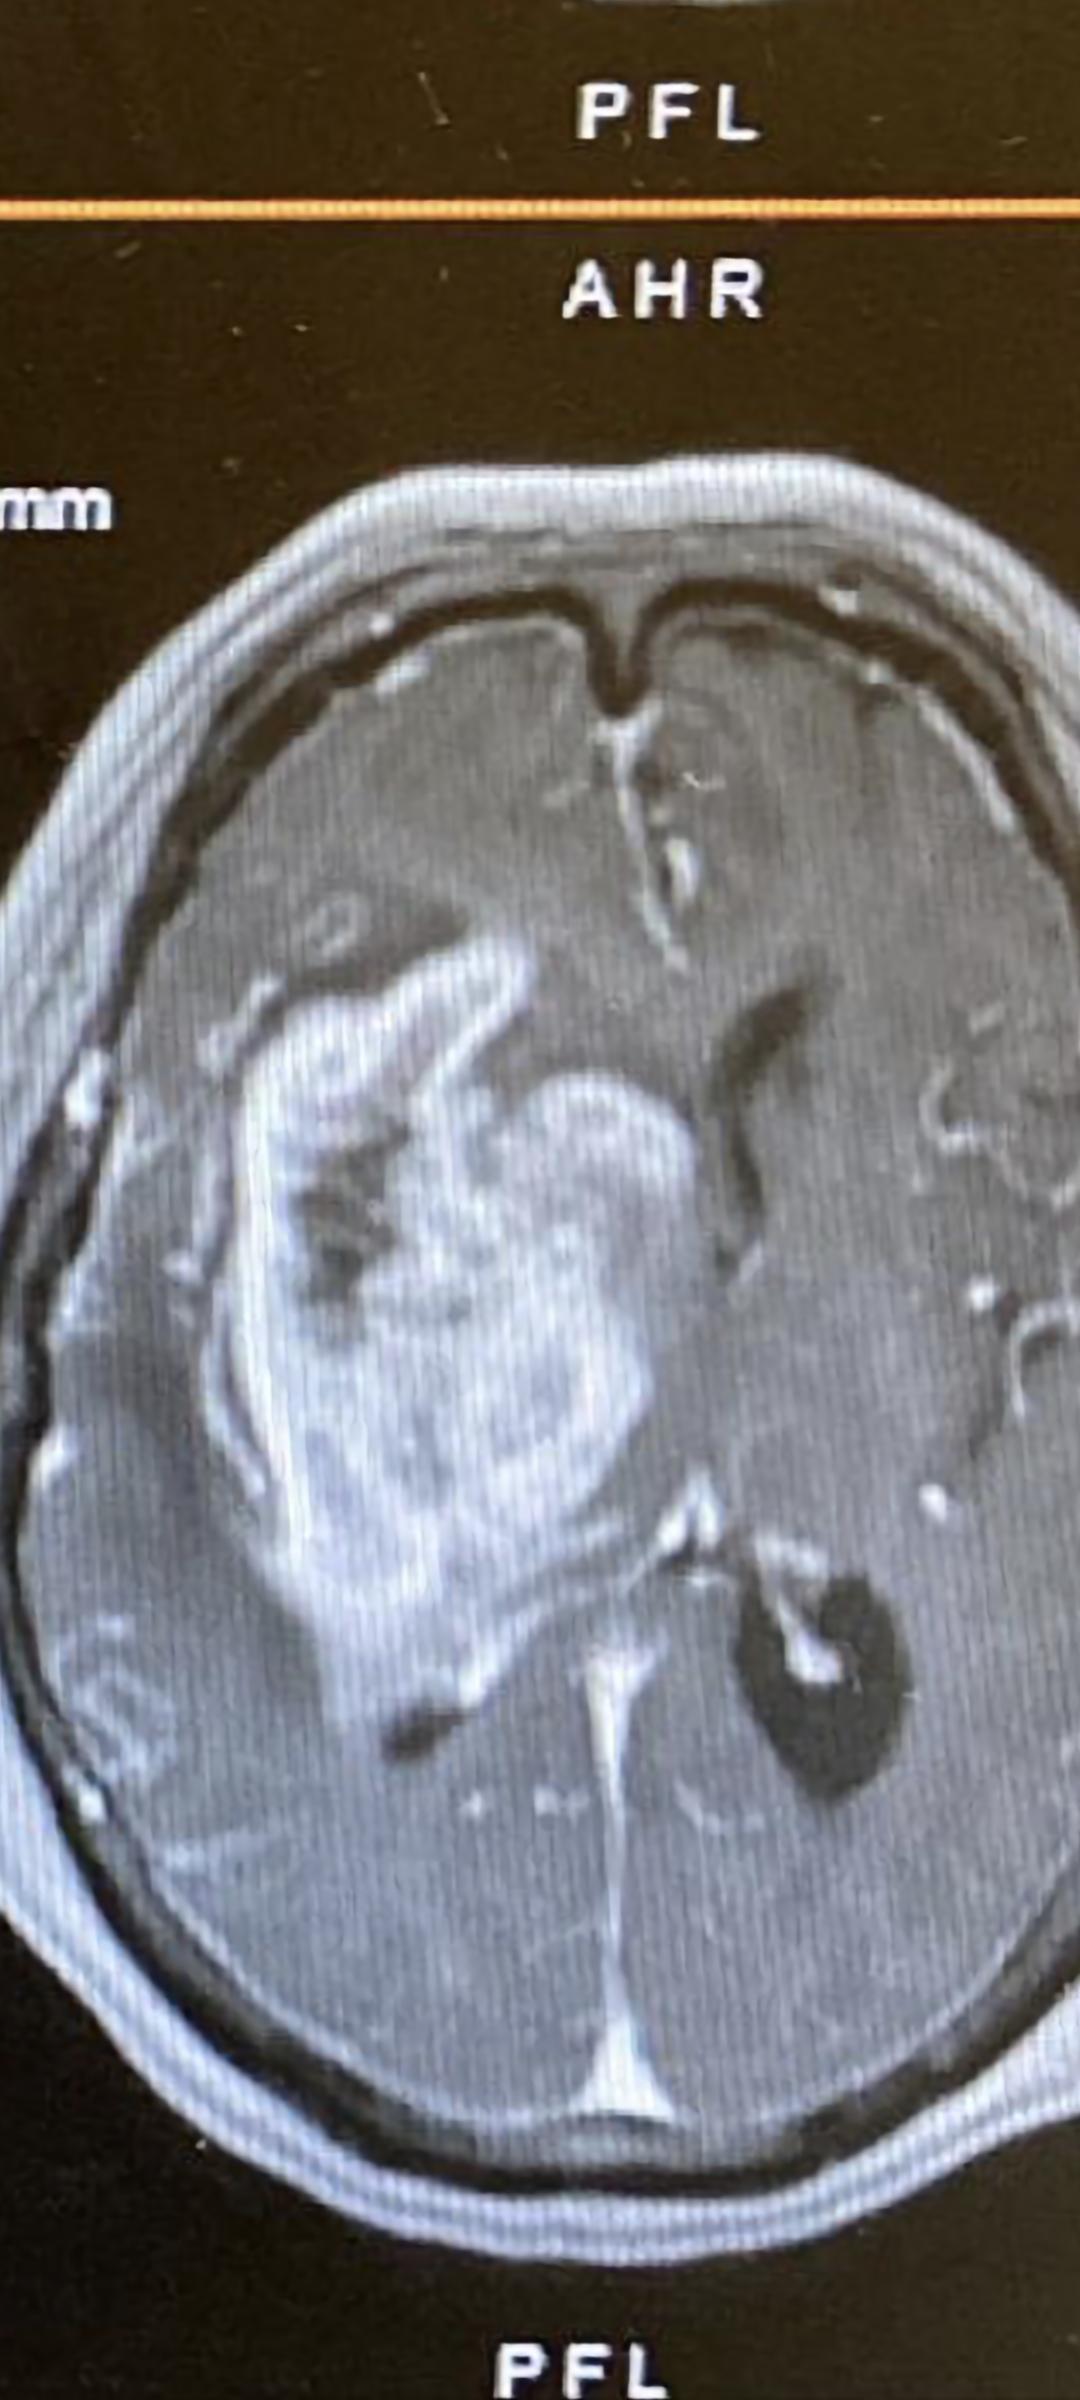

在了解這種生理反應後,想帶出第一種危險的頭痛,就是晨起頭痛。顧名思義,這頭痛是在早上發生,而且患者會痛醒,為何要發生在早上?正常人的呼吸在熟睡時比較慢和淺,特別在清晨,肺容積量減少,換氣相對減少的情況下導致血內二氧化碳濃度提高。如果患者有腦腫瘤,即腦組織容量已提高,血管因二氧化碳提高而擴張,腦內血液量也提高。顱內壓機制有兩項已提高,患者頭痛痛醒和嘔吐,嘔吐後才紓緩,因為腦內血液量下降,機制也從新平衡。所以晨起頭痛是包括頭痛痛醒,嘔吐和嘔吐後紓緩三點。有此症狀要馬上找神經外科醫生安排檢查,醫生多數建議做磁力共振掃描。